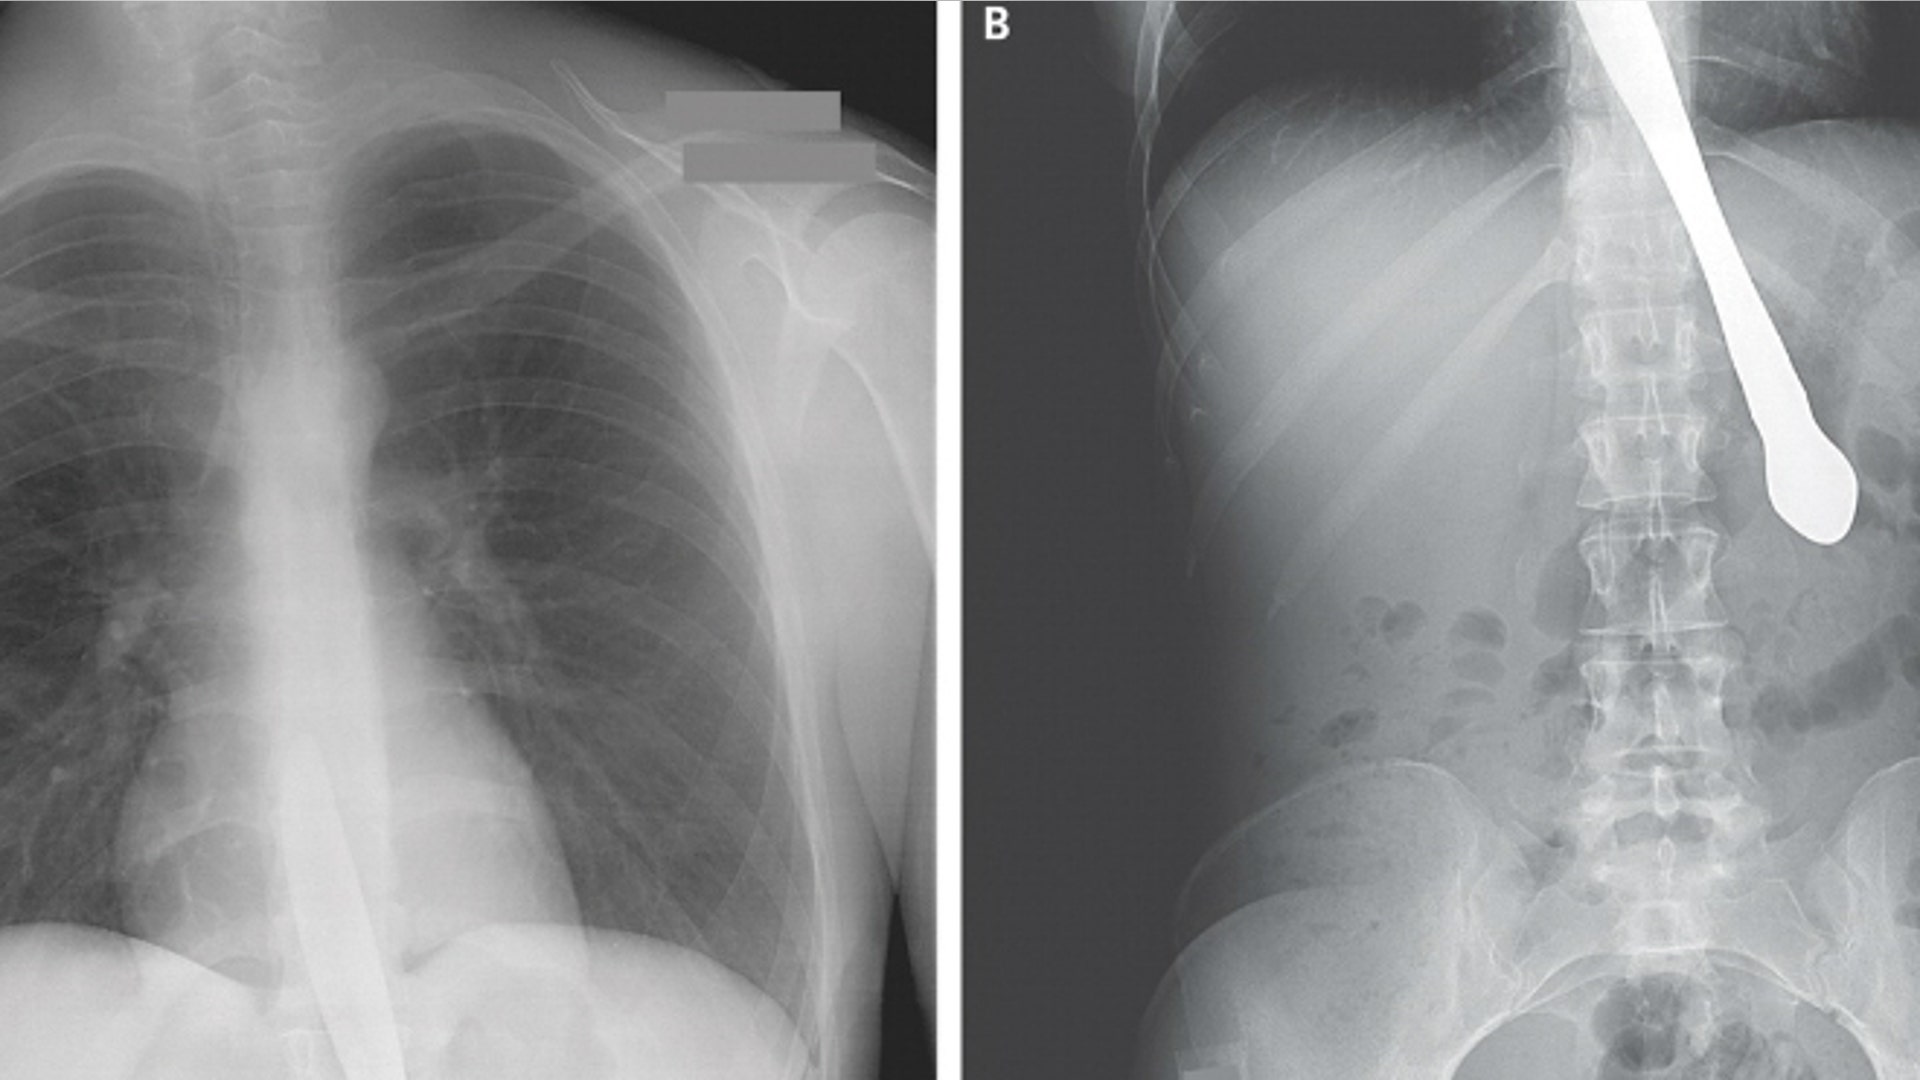

A 30-year-old woman swallowed a butter knife while attempting to prove to her friends that she had no gag reflex, according to an article in the New England Journal of Medicine. The knife lodged in the former bulimic's esophagus and proximal stomach. According to the journal, her husband said this is not the first time she has attempted this trick. Four years prior, she swallowed a knife and it was surgically removed. Doctors used a camera to remove the knife, and she was able to resume eating shortly thereafter.read moreNew England Journal of MedicineShare![yasserlopezxray]()

A 76-year-old woman went to the hospital complaining of weight loss and diarrhea, only to find she had a felt-tipped pen lodged in her stomach, according to the British Medical Journal. The woman told doctors she had accidentally swallowed a pen 25 years ago when she slipped while “interrogating a spot on her tonsil.” When doctors – and the woman’s husband didn’t believe her - an X-ray proved she was right. To the surprise of doctors, the pen was still in working order. A doctor wrote “hello” with it and then took a photo.read moreBritish Medical JournalShare